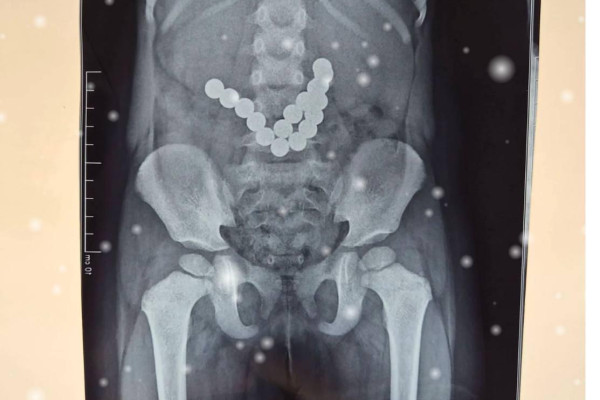

Ошто 2 жашар баланын ичегисинен 17 даана магнит чыгарылды

Ошто 17 магнитти жутуп алган эки жаштагы балага операция жасалды